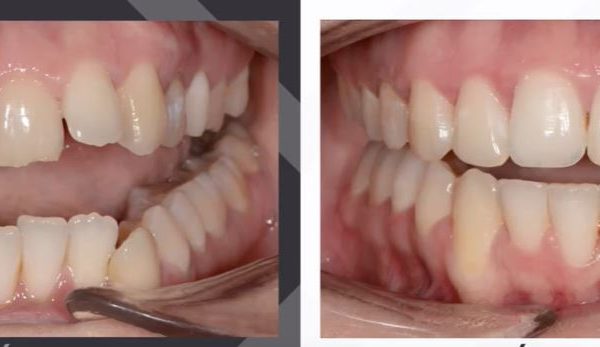

Az elmúlt évekből rengeteg szakmai referenciát tudnánk bemutatni, amelyek különböző fogszabályozási problémákat oldottak meg. Válogatva a több száz esetből, ezen az oldalon olyan képeket, információkat igyekeztünk bemutatni, amelyeknek a segítségével a jövőbeni pácienseinknek azt tudjuk üzenni: A Te fogsorod is lehet gyönyörű!

(Képeket a Pácienseink külön írásos beleegyezésével mutatjuk be!)